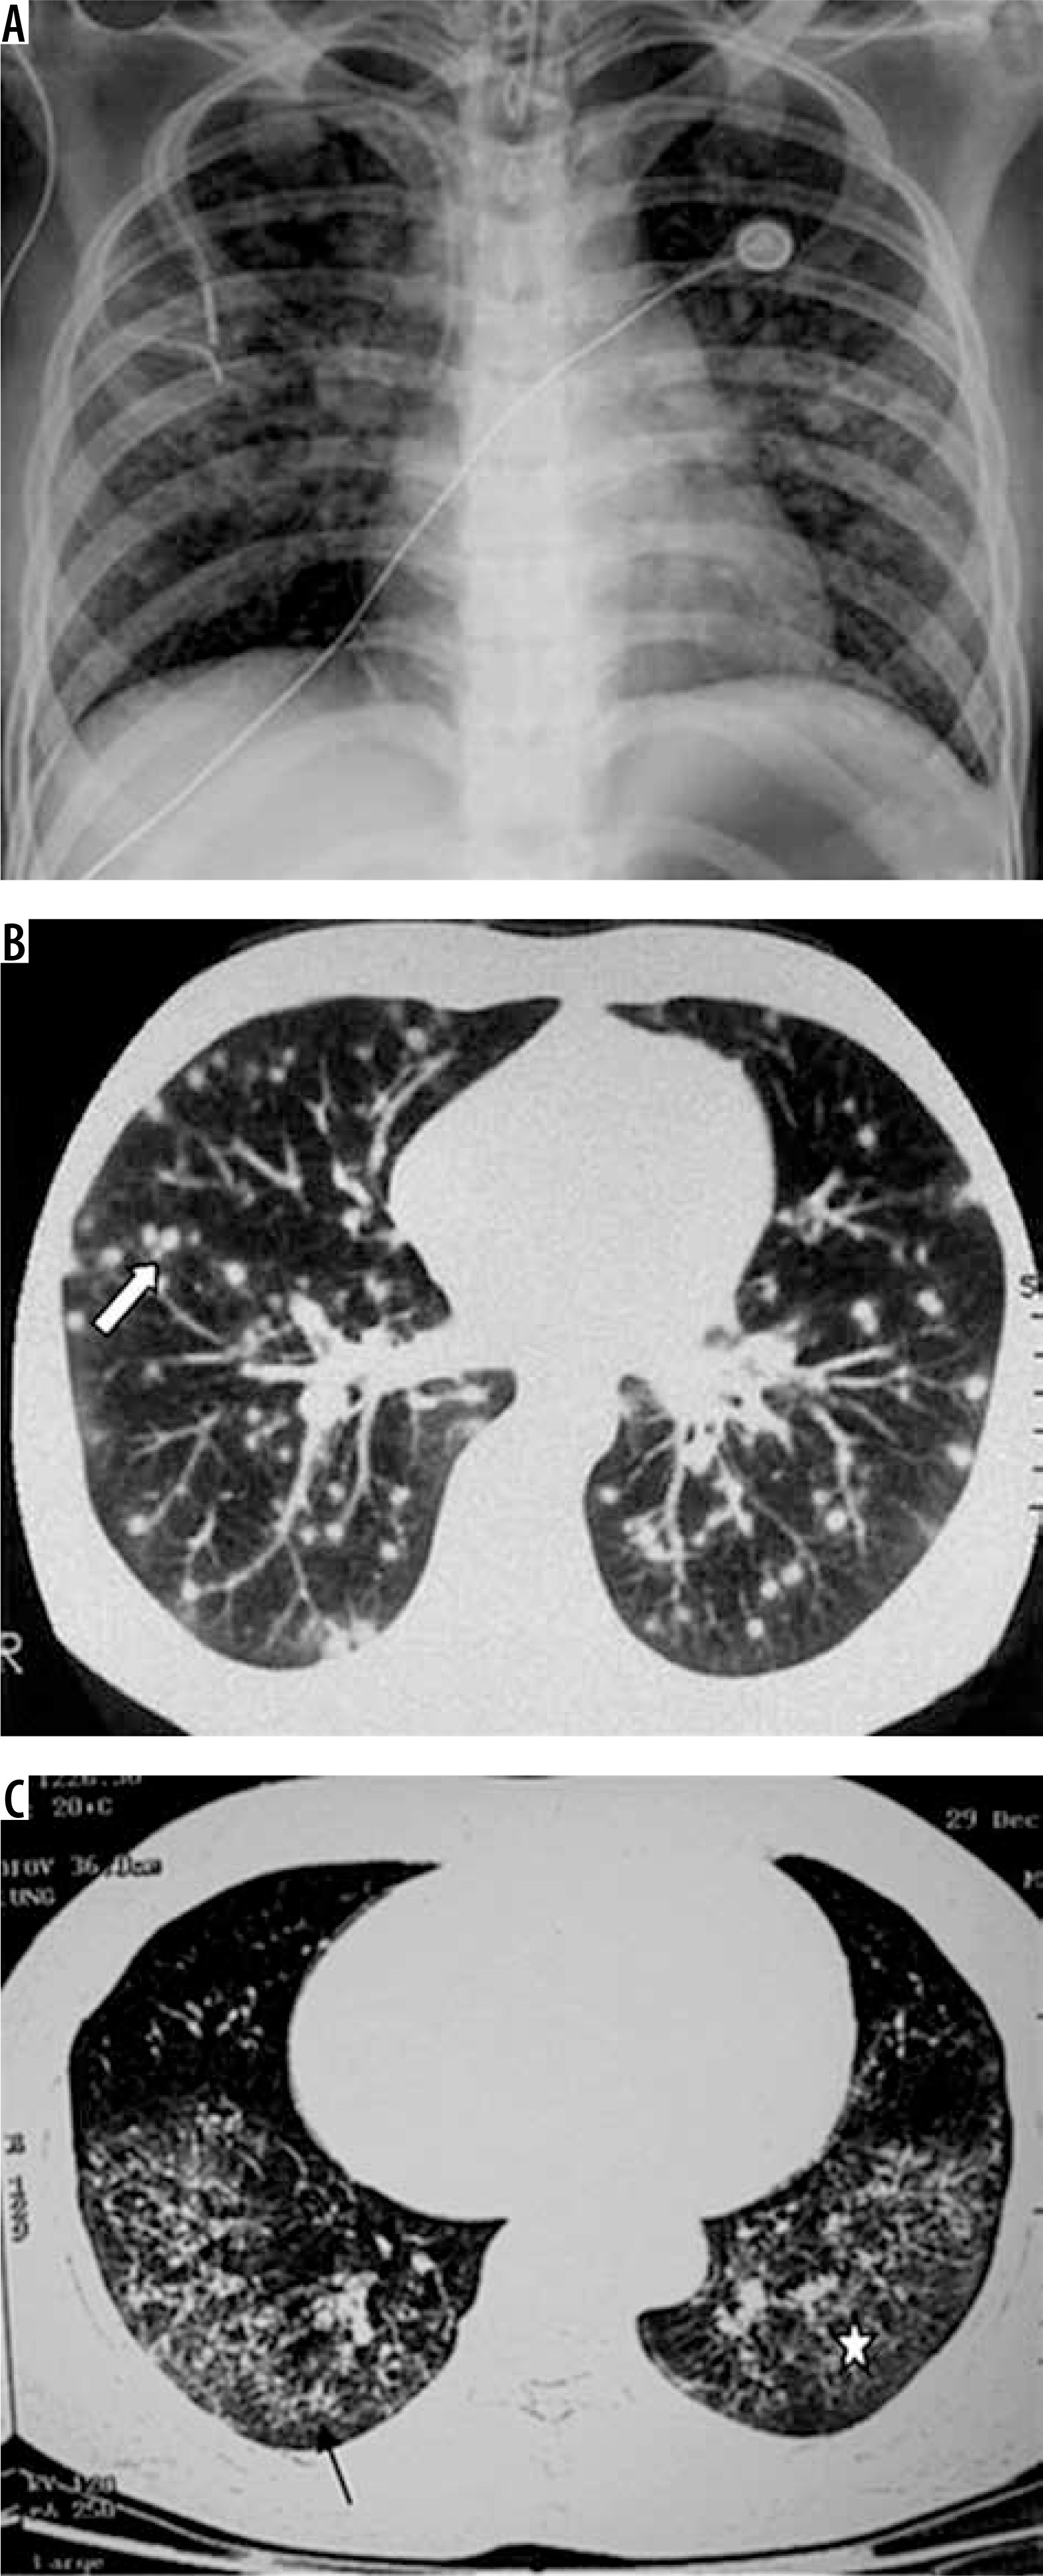

Figure 3

Patient with disseminated histoplasmosis. A) Chest radiograph shows presence of nodules in both lungs. B) Chest computed tomography (CT) shows small random nodules (arrow) in both lungs. C) Disseminated histoplasmosis in a different patient. Chest CT shows small nodules with intralobular septal thickening (black arrow) and ground glass opacities (asterisk) in both lungs